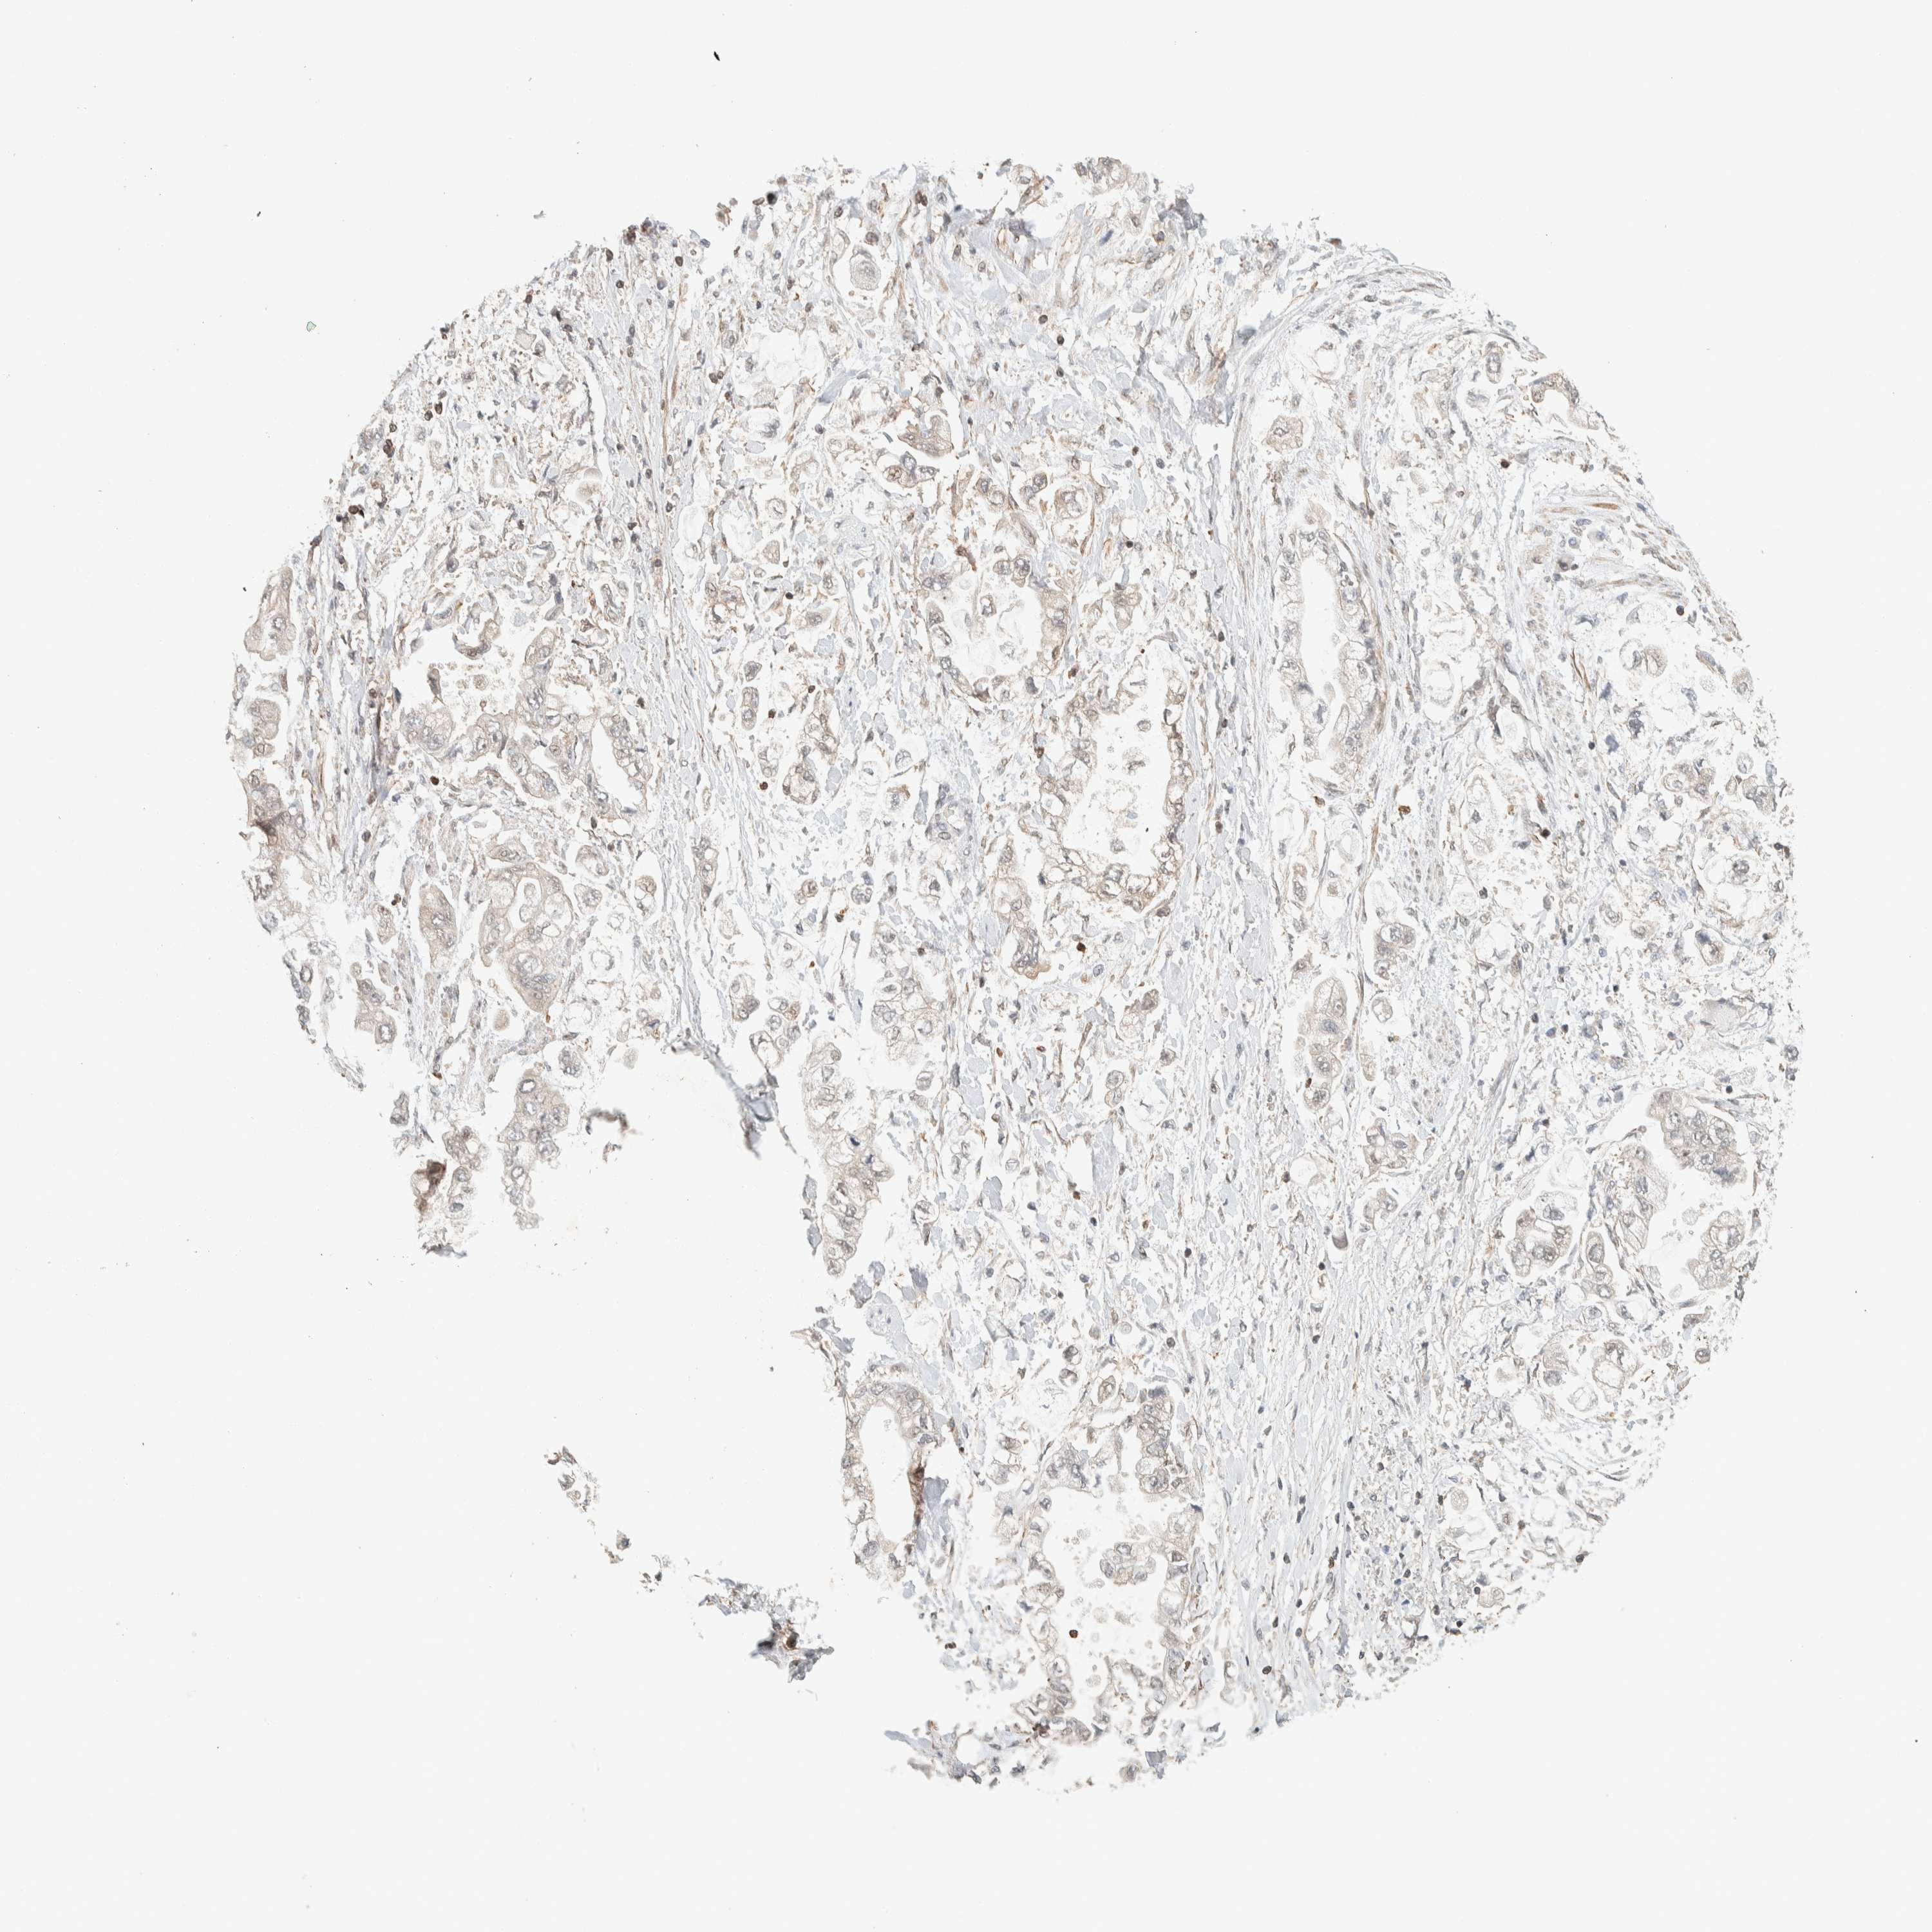

STOMACH CANCER - Protein expressioni

A mouse-over function shows sample information and annotation data. Click on an image to view it in a full screen mode. Samples can be filtered based on level of antibody staining by selecting one or several of the following categories: high, medium, low and not detected. The assay and annotation is described here.

Note that samples used for immunohistochemistry by the Human Protein Atlas do not correspond to samples in the TCGA dataset.

Antibody stainingi

Antibody staining in the annotated cell types in the current human tissue is reported as not detected, low, medium, or high, based on conventional immunohistochemistry profiling in selected tissues. This score is based on the combination of the staining intensity and fraction of stained cells.

Each image is clickable and will lead to virtual microscopy that enables deeper exploration of all samples and also displays staining intensity scores, fraction scores and subcellular localization as well as patient and tissue information for each sample.

Antibody HPA023399

Antibody HPA023822

Staining

High

Medium

Low

Not detected

Intensity

Strong

Moderate

Weak

Negative

Quantity

>75%

75%-25%

<25%

None

Location

Nuclear

Cytoplasmic/membranous

Cytoplasmic/membranous,nuclear

Adenocarcinoma, NOS